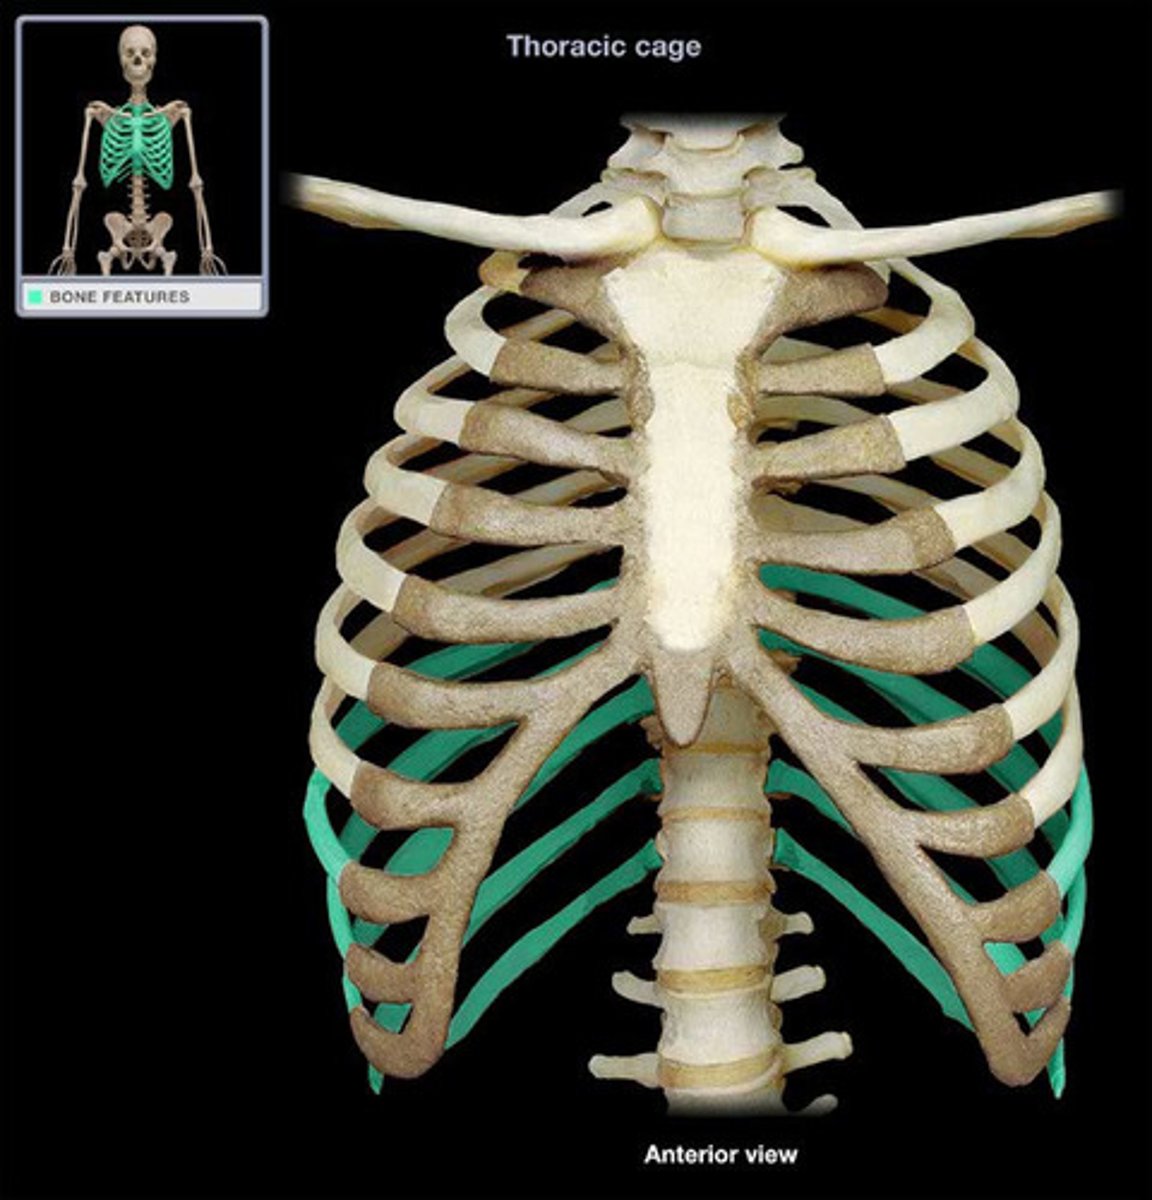

What makes up the thoracic cage?

sternum, ribs, and thoracic vertebrae

What is the function of the thoracic cage?

Protects heart, lungs, trachea, esophagus, and other thoracic organs, support upper limbs and provide muscle attachments

Which are the true ribs and what makes them "true" ?

1-7, attach directly to sternum via costal cartilage

Which are false ribs? Why?

ribs 8, 9, 10 (usually), attach directly to sternum but by the cartilage of the superior rib

Which are the "floating ribs" and why?

11-12, Don't attach in any way to sternum

manubrium of sternum

Articulates with ribs 1, 2, & clavicles. Sternocleidomastoid muscles also attach here.

suprasternal (jugular) notch

superior surface of manubrium; u shaped notch

clavicular notch of sternum

Site where manubrium articulates with the clavicles

costal notches of sternum

indentations on sternum where costal cartilages from the ribs articulate

sternal angle

Ridge between manubrium and body at second rib

Xiphoid process of sternum

(T10)

Midline marker for superior level of liver, central tendon of diaphram

inferior border border of heart

cartilaginous in young people. Bone after 40.

thoracic cage

ribs, sternum, thoracic vertebrae, encloses organs and moves for ventilation